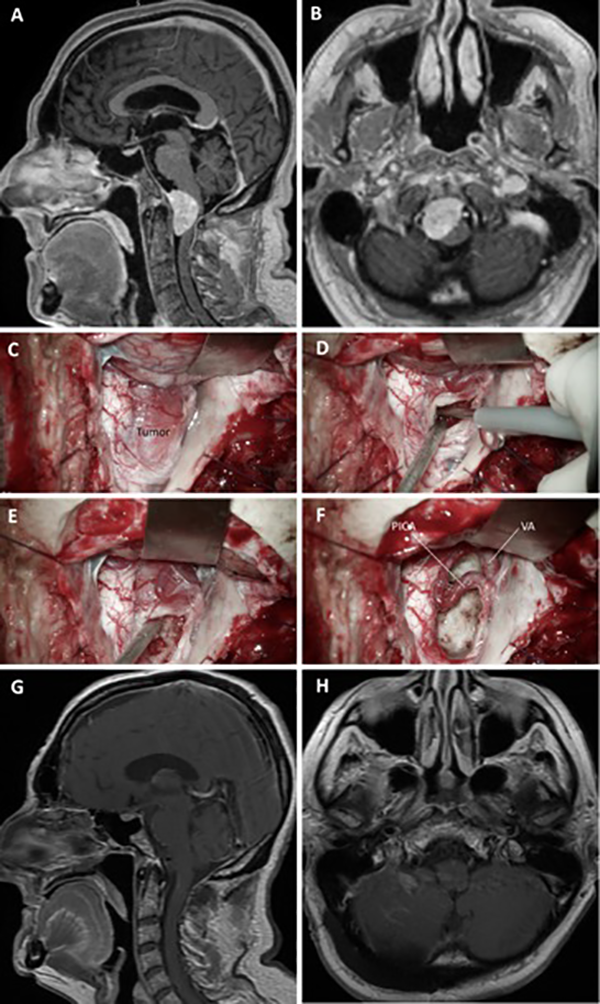

Figura 13.

Meningioma del foramen magno. A-B: RM preoperatoria; C-F: Hallazgos intraoperatorios; G-H: RM postoperatoria.